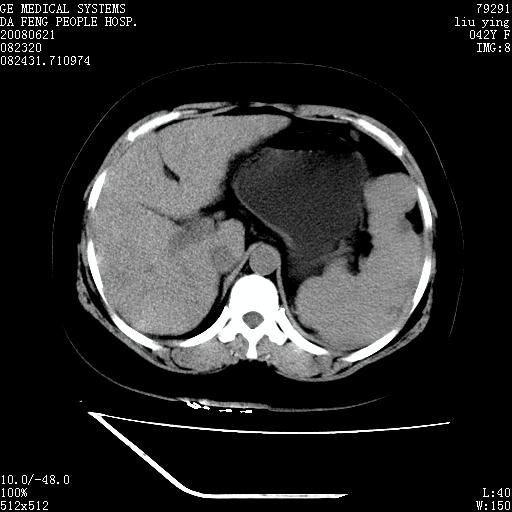

标题: CT14225:女性46岁。当地B超示肝内占位,来我院作CT检查。请 [打印本页]

标题: CT14225:女性46岁。当地B超示肝内占位,来我院作CT检查。请

肝内结节强化特点符合原发性肝癌表现,脾脏改变考虑为增大及先天发育所致。

动脉期病原灶明显强化高于肝密度且中央有无强化区,静脉期强化程度下降明显,延迟低于肝密度,考虑肝腺瘤可能性大,

符合肝癌表现,脾脏大(肝硬化?)

肝内结节强化特点:快进快出符合原发性肝癌表现

非常典型,肝ca,脾脏先天性发育异常,脾大

此患者虽然符合快进的特点,却不符合快出的特点,因为门脉期几乎是等密度,不符合肝癌的增强表现,所以我考虑肝局灶性结节增生可能性大

快进快出,符合肝癌表现。脾脏改变考虑为增大及先天发育所致。